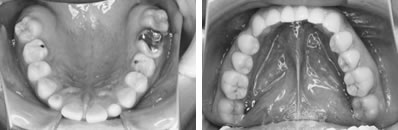

前歯の反対咬合と凸凹を解消した8歳

前歯の反対咬合と、それに合せて歯肉が下がっていることが心配されました。下顎の凸凹も問題でした。

上顎左側の2番目の永久歯(側切歯)が反対咬合です。まだ乳歯も多く残る歯並びですが、全体に凸凹が認められます。